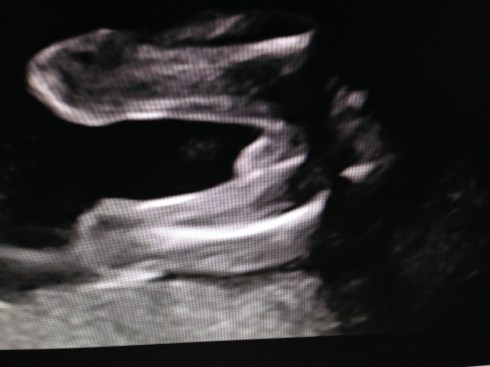

The ultrasound was performed on Friday, March 21, 2014 (at 19 weeks + 4 days). Our boy appeared healthy in all ways and weighed about 10 oz. His growth measurements were between 43% and 62% for his gestational age, and the heart rate was 147 bpm. The placenta is posterior and without previa. My cervix is long. Excellent!

We received a DVD of the scan. I took this short video clip with my phone, that shows baby’s face: moving his jaw, yawning, moving his tongue, and even smiling. You can also see his forearm in front of his face. Watch it again and look for the heart beating. Precious!!

I took these images by pausing the DVD and taking screen shots: